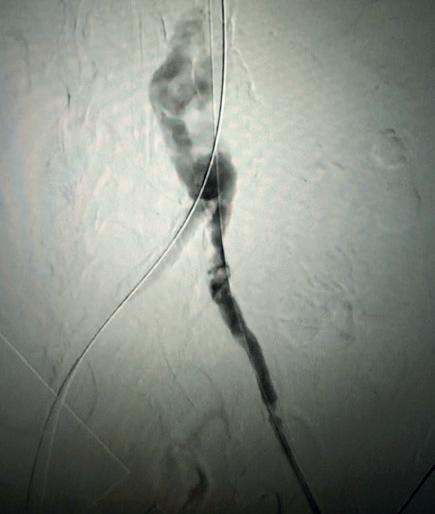

Case 1: The Shockwave L6 device in the setting of FEVAR and complex iliac stenosis

An 82-year-old man with a history of coronary artery disease (CAD), hypertension, hyperlipidemia, and peripheral arterial disease (PAD) presents with rest pain as well as

a large pararenal abdominal aortic aneurysm (AAA). His computed tomography angiography (CTA) revealed very dense and highly diseased iliac vessels with calcium deposition along most of the bilateral common iliac distribution.

The minimum luminal diameter (MLD) of the common iliac arteries measured roughly 4.5mm; however, the

“My experience with this system has taught me that appropriate balloon sizing is the single-most important predictor of a successful outcome”

healthy reference vessel diameter (RVD) was 9.5mm. He would require a fenestrated repair of the AAA along with complex iliac stenosis treatment, and extensive bilateral common femoral endarterectomies.

Further, we were concerned we would not be able to advance the 19F fenestrated graft. The endograft was prepared, and then both femoral arteries were exposed. We attempted delivery of the endograft via the right common iliac access. This failed. We then attempted delivery on the contralateral side. Despite multiple attempts, we made little progress. A 10x30mm Shockwave L 6 catheter was selected, and a total of 150 pulses were delivered to each iliac artery at just 4atm. This not only allowed for the delivery of our FEVAR graft but also the full unrestricted expansion of the endograft limbs in the common iliac arteries.

At the completion of the AAA, we took extra time to perform endarterectomies of the deep femoral arteries. His completion CT scan revealed a good seal of the AAA, patency of the renal fenestrations and unrestricted flow to the bilateral femoral arteries.

Figure 1. Pre-procdural CTA

Figure 4. Graft delivery

Figure 1. Pre-procedural angiogram

Figure 2. Pre-procedural angiogram

Figure 5. Final angiogram

Figure 2. IVL treatment angiogram

Figure 3. Post-IVL angiogram

Figure 6. Post-procedural CTA